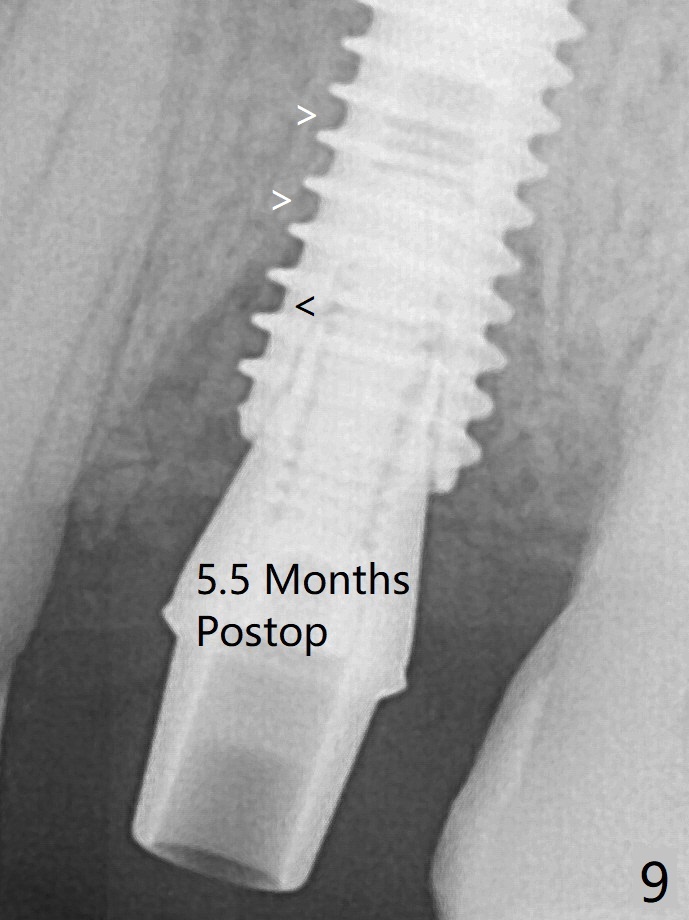

Due to short apical bone (Fig.5,7), a long dummy implant (3.8x15 mm) is placed with periimplant space immediately post extraction (Fig.1 *). The final implant is larger (4.5x15 mm) with simultaneous periimplant bone graft (Fig.2 <,当时骨粉一定用的多,压得紧,好像进入螺纹). The native bone (higher in bone density, Fig.9 white arrowheads, as compared to black one (for bone graft)) appears to have grown into the space between implant threads 5.5 months postop. Sinus Lift Last Next XinWei, DDS, PhD, MS 1st edition 06/21/2019, last revisionn 06/13/2021